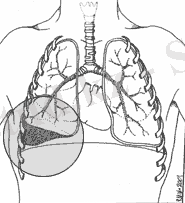

Гемоморакс деп плевраға қан жиналуды айтады.

(Классификация П. А. Куприянов (гемоторакс) :

Кіші гемоторакс (500-600 мл қан қабырға диафрагмасының синусында), асқынбайды және 10-12 тәулікте қалпына келеді.

Орташа гемоторакс (1000-1500 мл ), аускультация әдісі арқылы тексергенде жауырын үстінде дем алу әлсіз естіледі.

Үлкен гемоторакс плврада қан 1000мл жоғары болады. Клиникада 2-3 қабырға аралығының артында анықталады. Өкпеге перкусия жасағанда тұйық дыбыс естіледі. Асқынса гемопневмотороксқа алып келеді.

ГЕМОТОРАКС